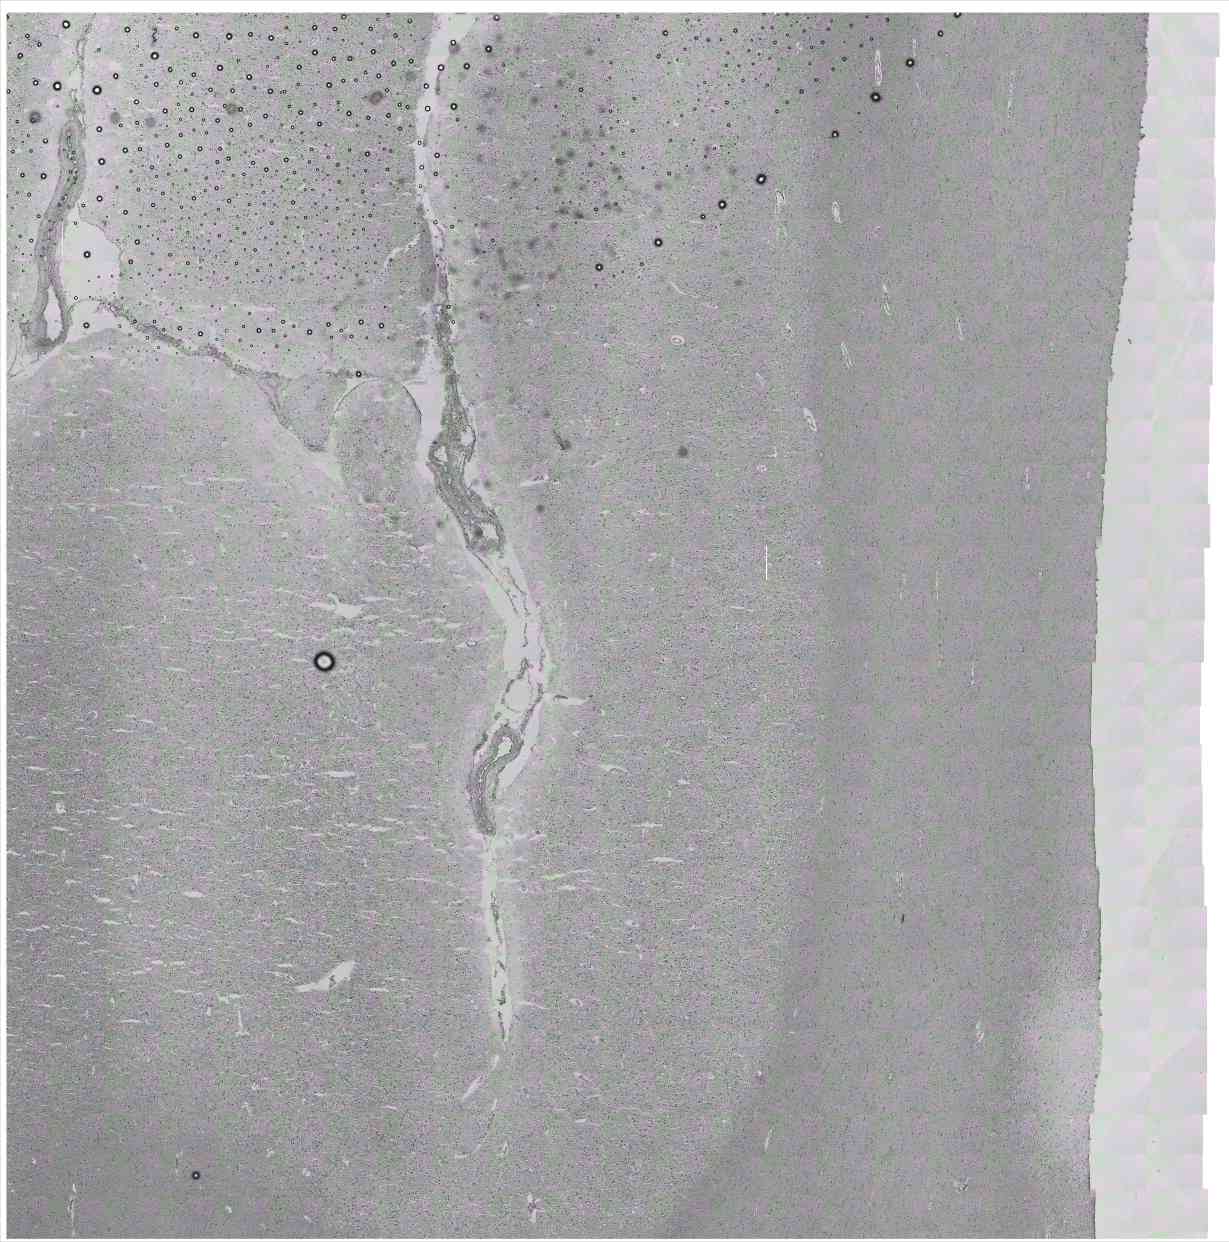

Chip 019 Well D2